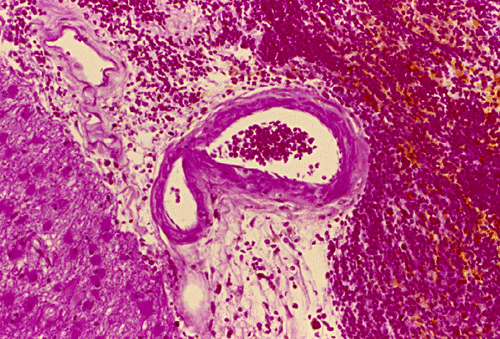

Histopathology: The hemorrhage, not surprisingly, is composed of blood (Panel B). At the periphery of the hemorrhage are areas that are heavily infiltrated by macrophages accompanied by substantial hemosiderin depositions (Panel C). On medium magnification, the blood vessel walls seems to be thickened and some ill-defined deposition are present in the wall (Arrow in Panel D). Immunohistochemistry for amyloid-b (Ab) was performed and the depositions in the vessel wall are positive.

Microscopically, the pathology of hemorrhage is not different from that of hemorrhage due to other causes. However, the blood vessels, particular the arterioles and the leptomeningeal vessels appear to have thickened wall and some clumpy irregular, eosinophilic depositions may be seen.   The depositions are also positive for periodic acid Schiff stain. The affected vessels in Ab caused CAA often have segmental dilatations, microaneurysm formation, and fibrinoid necrosis. The small muscle layer is often destroyed. In severely affected vessels, a double-barrel vessel wall is present.The amyloid depositions will stain bright orange-red with Congo red and will give a green birefrigence under polarized light.  In addition, immunohistochemical detection would be positive for Ab in many of the sporadic cases. P-component which almost always co-deposit with amyloid can also be detected by immunohistochemistry. At the ultrastructural level, Ab amyloid appears as clumps and bundles of straight filaments of 10 nm in diameter.